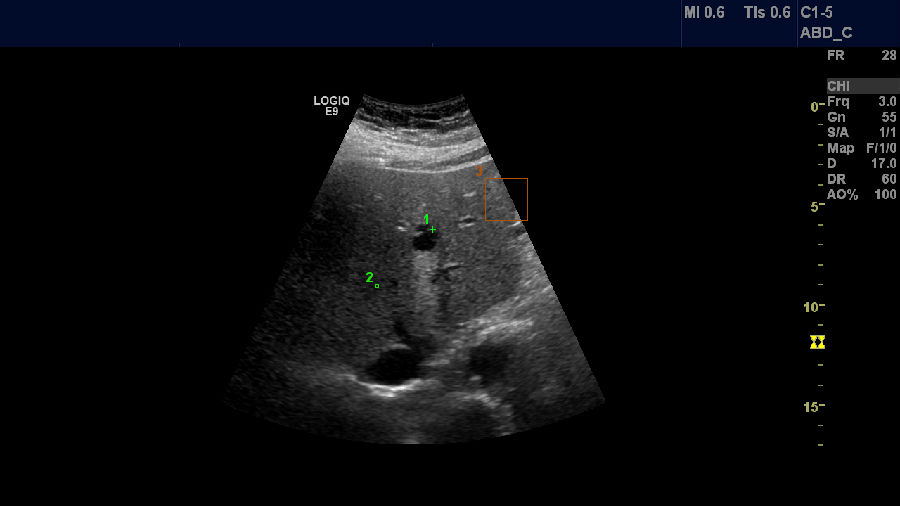

肝硬化、腹水

肋间斜切,肝硬化,腹水